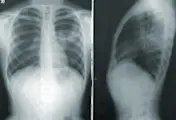

Pulmonolog wysnuwa podejrzenie azbestozy zwykle już na podstawie zgłaszanych przez pacjenta objawów i wyniku badania RTG. Azbestoza daje w RTG obraz sugerujący śródmiąższowe włóknienie płuc. Specjalista poszerzy również diagnostykę o inne badania dodatkowe, w tym:

HRCT, czyli wysokiej czułości tomografia komputerowa – badanie to pozwoli na bardzo dokładną ocenę Twojej tkanki płucnej. Jeśli zmagasz się z azbestozą, w miąższu płuc będą widoczne rozsiane zwłóknienia miąższu, pogrubienie i zwłóknienia opłucnej;